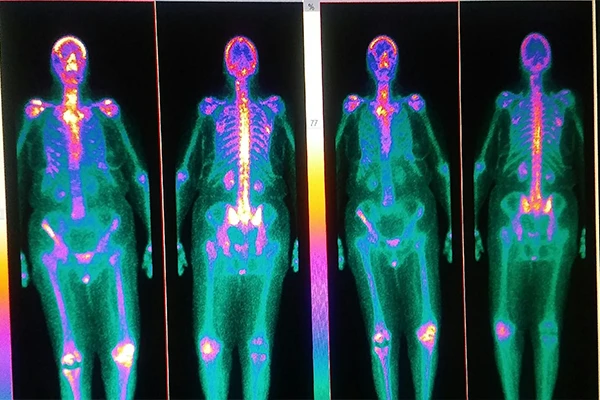

Nuclear Medicine Explained: An Overview of PET and SPECT

Understand how radiotracers are used to image physiological function with PET and SPECT scans.